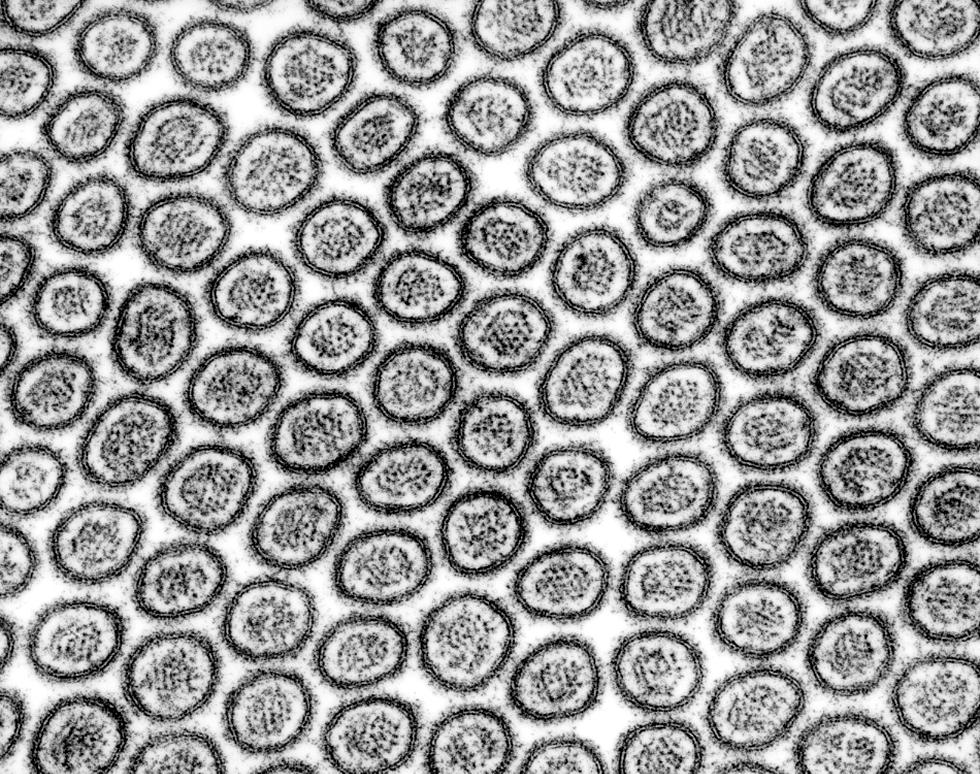

Mumps virus